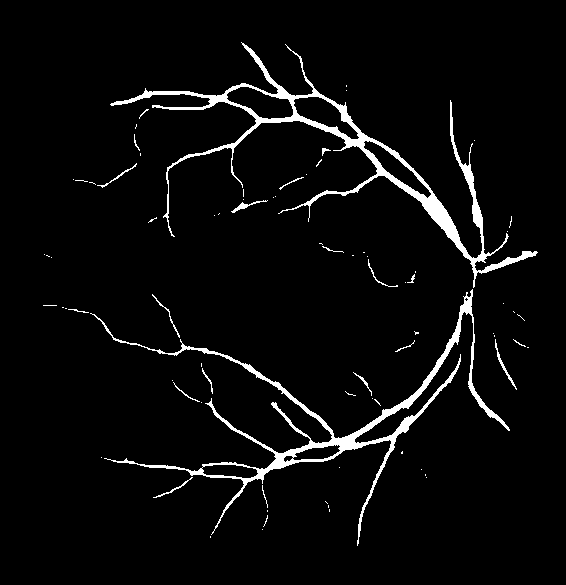

Figure 6: Visual results after level-II balancing.

Impact of Level-II Balancing: This section analyzes the impact of applying Level-II balancing on top of Level-I balancing to the same sample images as in the previous sub-section. Specifically, the outcomes of applying Level-I and Level-II balancing are compared and graphically demonstrated in Figure 6. The application of Level-II balancing results in a significant performance boost over Level-I balancing, as indicated by higher values of all performance measures. Similarly, Figure 6 shows the visual outcomes of Level-II balancing for the sample DRIVE images along with their ground truths. The output segmentation masks show the detection of thin retinal blood vessels much closer to the ground truth binary mask than the images for Level-I balancing. The red rectangle is highlighted as a focus area for conveniently comparing the results. It can be concluded from comparing the results that Level-II balancing detects most of the vessel’s pixels, especially thin vessels, thereby significantly improving the sensitivity.